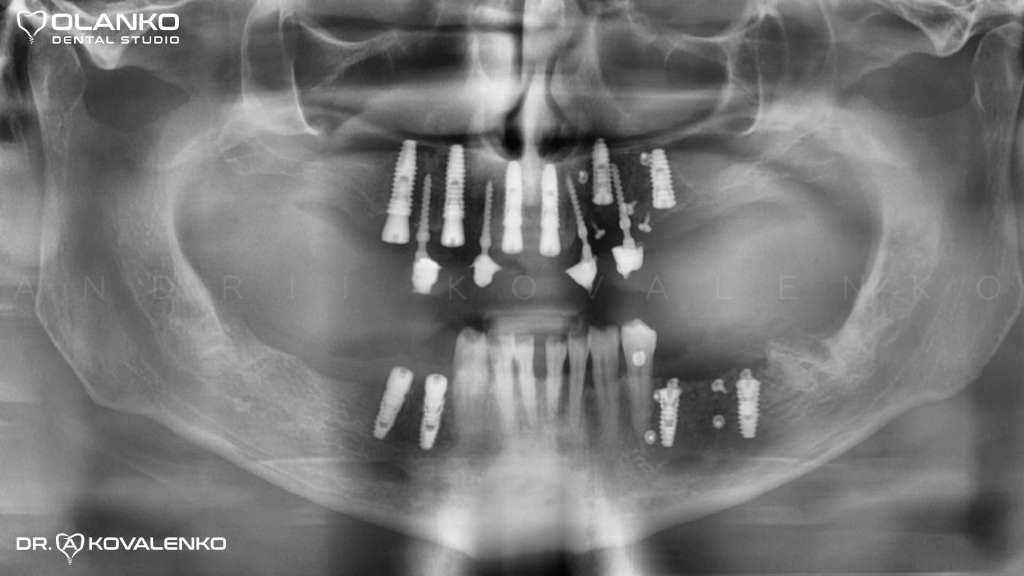

Одонтома нижней челюсти: фотографии и медицинская информация

Раздел: Фотобанк решений